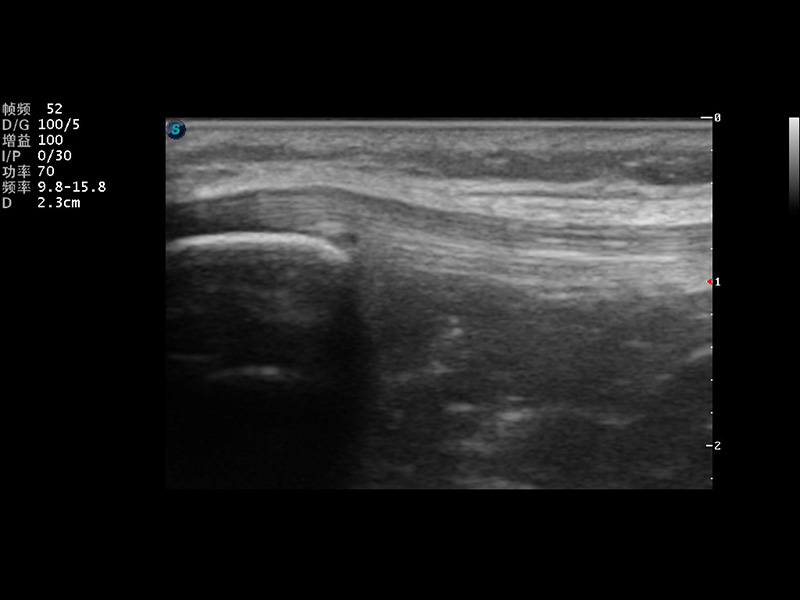

VIS平台设计

μ-Scan微米成像